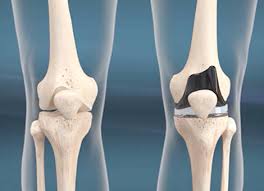

무릎 인공관절 수술, 왜 필요한가요?

무릎관절은 체중을 가장 많이 지탱하는 관절입니다. 나이가 들수록 연골은 점차 마모되고, 충격을 흡수하는 능력도 감소합니다. 이로 인해 통증, 뻣뻣함, 운동 제한이 생기며, 이런 증상이 악화되면 인공관절 수술이 필요해집니다.

퇴행성 관절염 외에도 류마티스 관절염이나 외상 후 관절 손상이 심각할 경우 수술이 권유되며, 수술을 통해 환자는 통증 없이 보행이 가능해지고 일상생활로 복귀할 수 있게 됩니다.